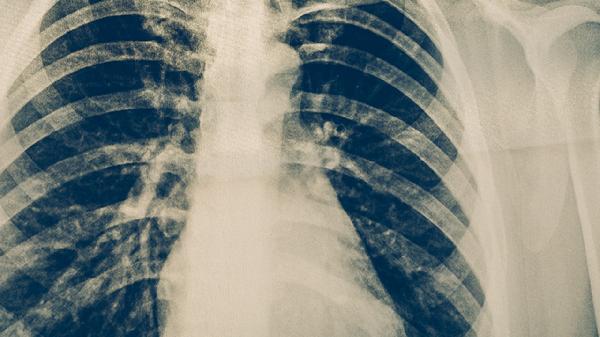

完成治疗后应每3-6个月进行胸部X线或CT检查,连续随访2年。出现咳嗽咳痰超过2周、低热盗汗、体重下降等可疑症状时需立即就诊。痰涂片和痰培养检查能早期发现细菌学复发。